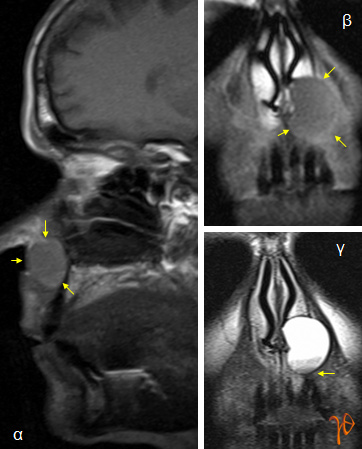

Αντίθετα στην μαγνητική τομογραφία απεικονίστηκε καλώς αφοριζόμενη σφαιροειδής βλάβη μεγίστης διαμέτρου περίπου 2,5 εκατοστών, εδραζόμενη στο χειλικό πετάλο της άνω γνάθου, επί του οποίου είχε προκαλέσει εντύπωμα, και εκτεινόμενη από την αριστερή κάτω ρινική κόγχη μέχρι την μέση γραμμή και μέχρι το ύψος των ακρορριζίων των προσθίων οδόντων(Εικόνες 3 και 4).

Εικόνα 4α: Η έκταση της βλάβης στο οβελιαίο επίπεδο(βέλη), 4β και 4γ: Μετωπιαίες τομές(Τ1 και Τ2 ακολουθία, αντίστοιχα) με την έκταση της βλάβης και την τοπογραφική σχέση των κατώτερων ορίων της με τα ακρορρίζια των δοντιών(βέλη).